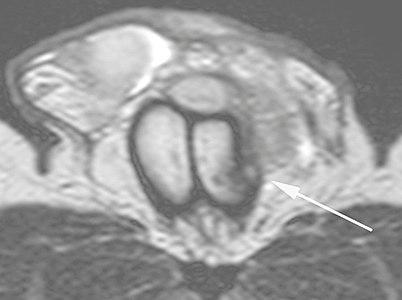

Ultrasound examination is able to depict the tunica albuginea tear in the majority of cases (as a hypoechoic discontinuity in the normally echogenic tunica). In a study on 25 patients, Zare Mehrjardi et al. concluded that ultrasound is unable to find the tear just when it is located at the penile base. In their study magnetic resonance imaging (MRI) accurately diagnosed all of the tears (as a discontinuity in the normally low signal tunica on both T1- and T2-weighted sequences). They concluded that ultrasound should be considered as the initial imaging method, and MRI can be helpful in cases that ultrasound does not depict any tear but clinical suspicions for fracture are still high. In the same study, authors investigated accuracy of ultrasound and MRI for determining the tear location (mapping of fracture) in order to perform a tailored surgical repair. MRI was more accurate than ultrasound for this purpose, but ultrasound mapping was well correlated with surgical results in cases where the tear was clearly visualized on ultrasound exam.[10] The advantage of ultrasound in the diagnosis of penile fracture is unrivaled when its noninvasive, cost-effective, and nonionising nature are considered.[11]

In the ultrasound examination, a lesion of the tunica albuginea presents as an interruption in (loss of continuity of) the echoic line representing it (Figure 4). Small, moderate, or broad hematomas demonstrate the extent of that discontinuity. Intracavernous hematomas, sometimes without the presence of a tunica albuginea fracture, can be observed when there is a lesion of the smooth muscle of the trabeculae surrounding the sinusoid spaces or the subtunical venular plexus.[2]

In 10-15% of penile traumas, there can be an accompanying urethral lesion. When blood is observed in the urethral meatus, contrast-enhanced evaluation of the urethra is necessary. In cases in which the ultrasound findings are inconclusive, the use of magnetic resonance imaging can facilitate the diagnosis and is recommended by various authors.[2]